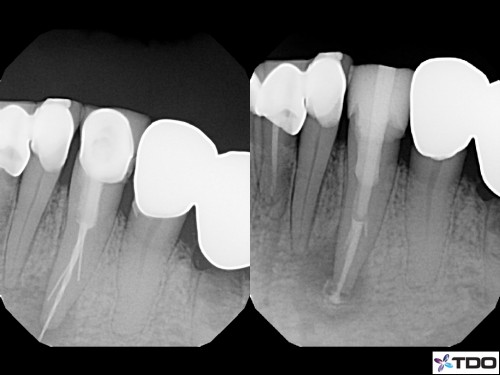

Perforation Management

The initial endodontic treatment was done a few years back and the conventional radiograph suggests […]